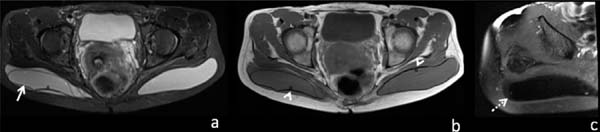

Oranges et al10 por sua vez, fizeram revisão da literatura que evidenciou uma taxa global de complicações de 30,5% para cirurgias estéticas de implante glúteo, sendo as mais prevalentes: deiscência da ferida operatória (8,1%), seroma (4,4%), infecção (3,2%) (Figura 5) e revisão do implante (3,1%). Outras complicações relatadas, porém, menos frequentes, são: rotura da prótese (Figura 6), deslocamento (Figura 7) e contratura (Figura 8).

O silicone líquido é tão denso quanto ou ligeiramente mais denso que as partes moles na tomografia. Na RM, tende a demonstrar intensidade de sinal intermediária ou discretamente maior que o sinal da água nas imagens ponderadas em T1, e intensidade variável em imagens ponderadas em T2, possivelmente em razão de diferentes viscosidades, sendo o silicone de alta viscosidade geralmente mais hipointenso em T2 6,7,8,16,27,28.

Na sequência específica para silicone, com supressão do sinal da água e da gordura, apresenta sinal alto19.

Como o silicone reside permanentemente nos tecidos, a remoção cirúrgica pode ser a única maneira de tratar os problemas crônicos. Porém, a remoção cirúrgica do silicone pode ser muito difícil para o cirurgião e desfigurante para o paciente. A RM pré-operatória com sequências específicas para silicone pode ser útil na definição e localização do material antes de qualquer tentativa cirúrgica, para localizar o silicone e facilitar a identificação e a remoção pelo cirurgião8.

A resposta tecidual do hospedeiro após a injeção de silicone resulta na formação de granulomas6 (Figura 15). Reações granulomatosas podem ocorrer semanas a décadas após a injeção7.

Pequenas complicações incluem reação no local da injeção, eritema, edema e cicatrizes12. Devido às impurezas no silicone e às condições não estéreis sob as quais as injeções frequentemente ocorrem, esses procedimentos podem ser complicados por celulite crônica, abscessos e miosite. Outras complicações locais da injeção de silicone incluem migração, hiperpigmentação e fibrose da pele, necrose, ulceração, fístula, desfiguração6.